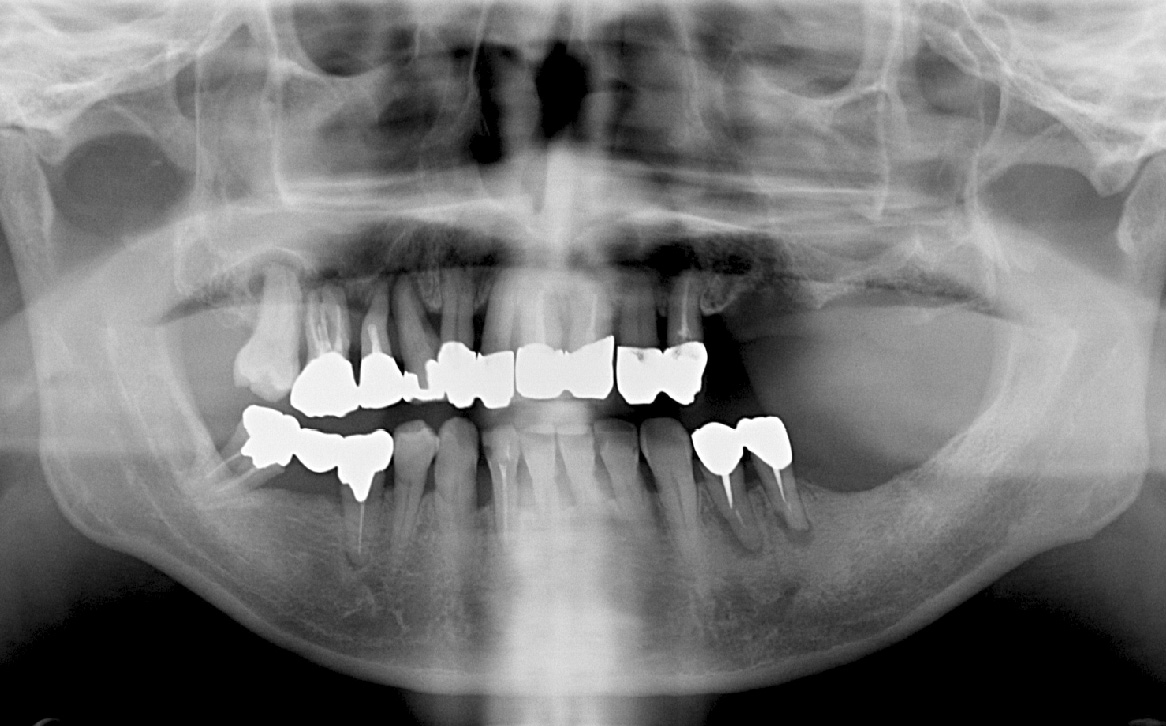

• Before

歯周病でグラグラな歯と合わなくなった被せなど全部抜歯してオールオン4とザイゴマにて治療。